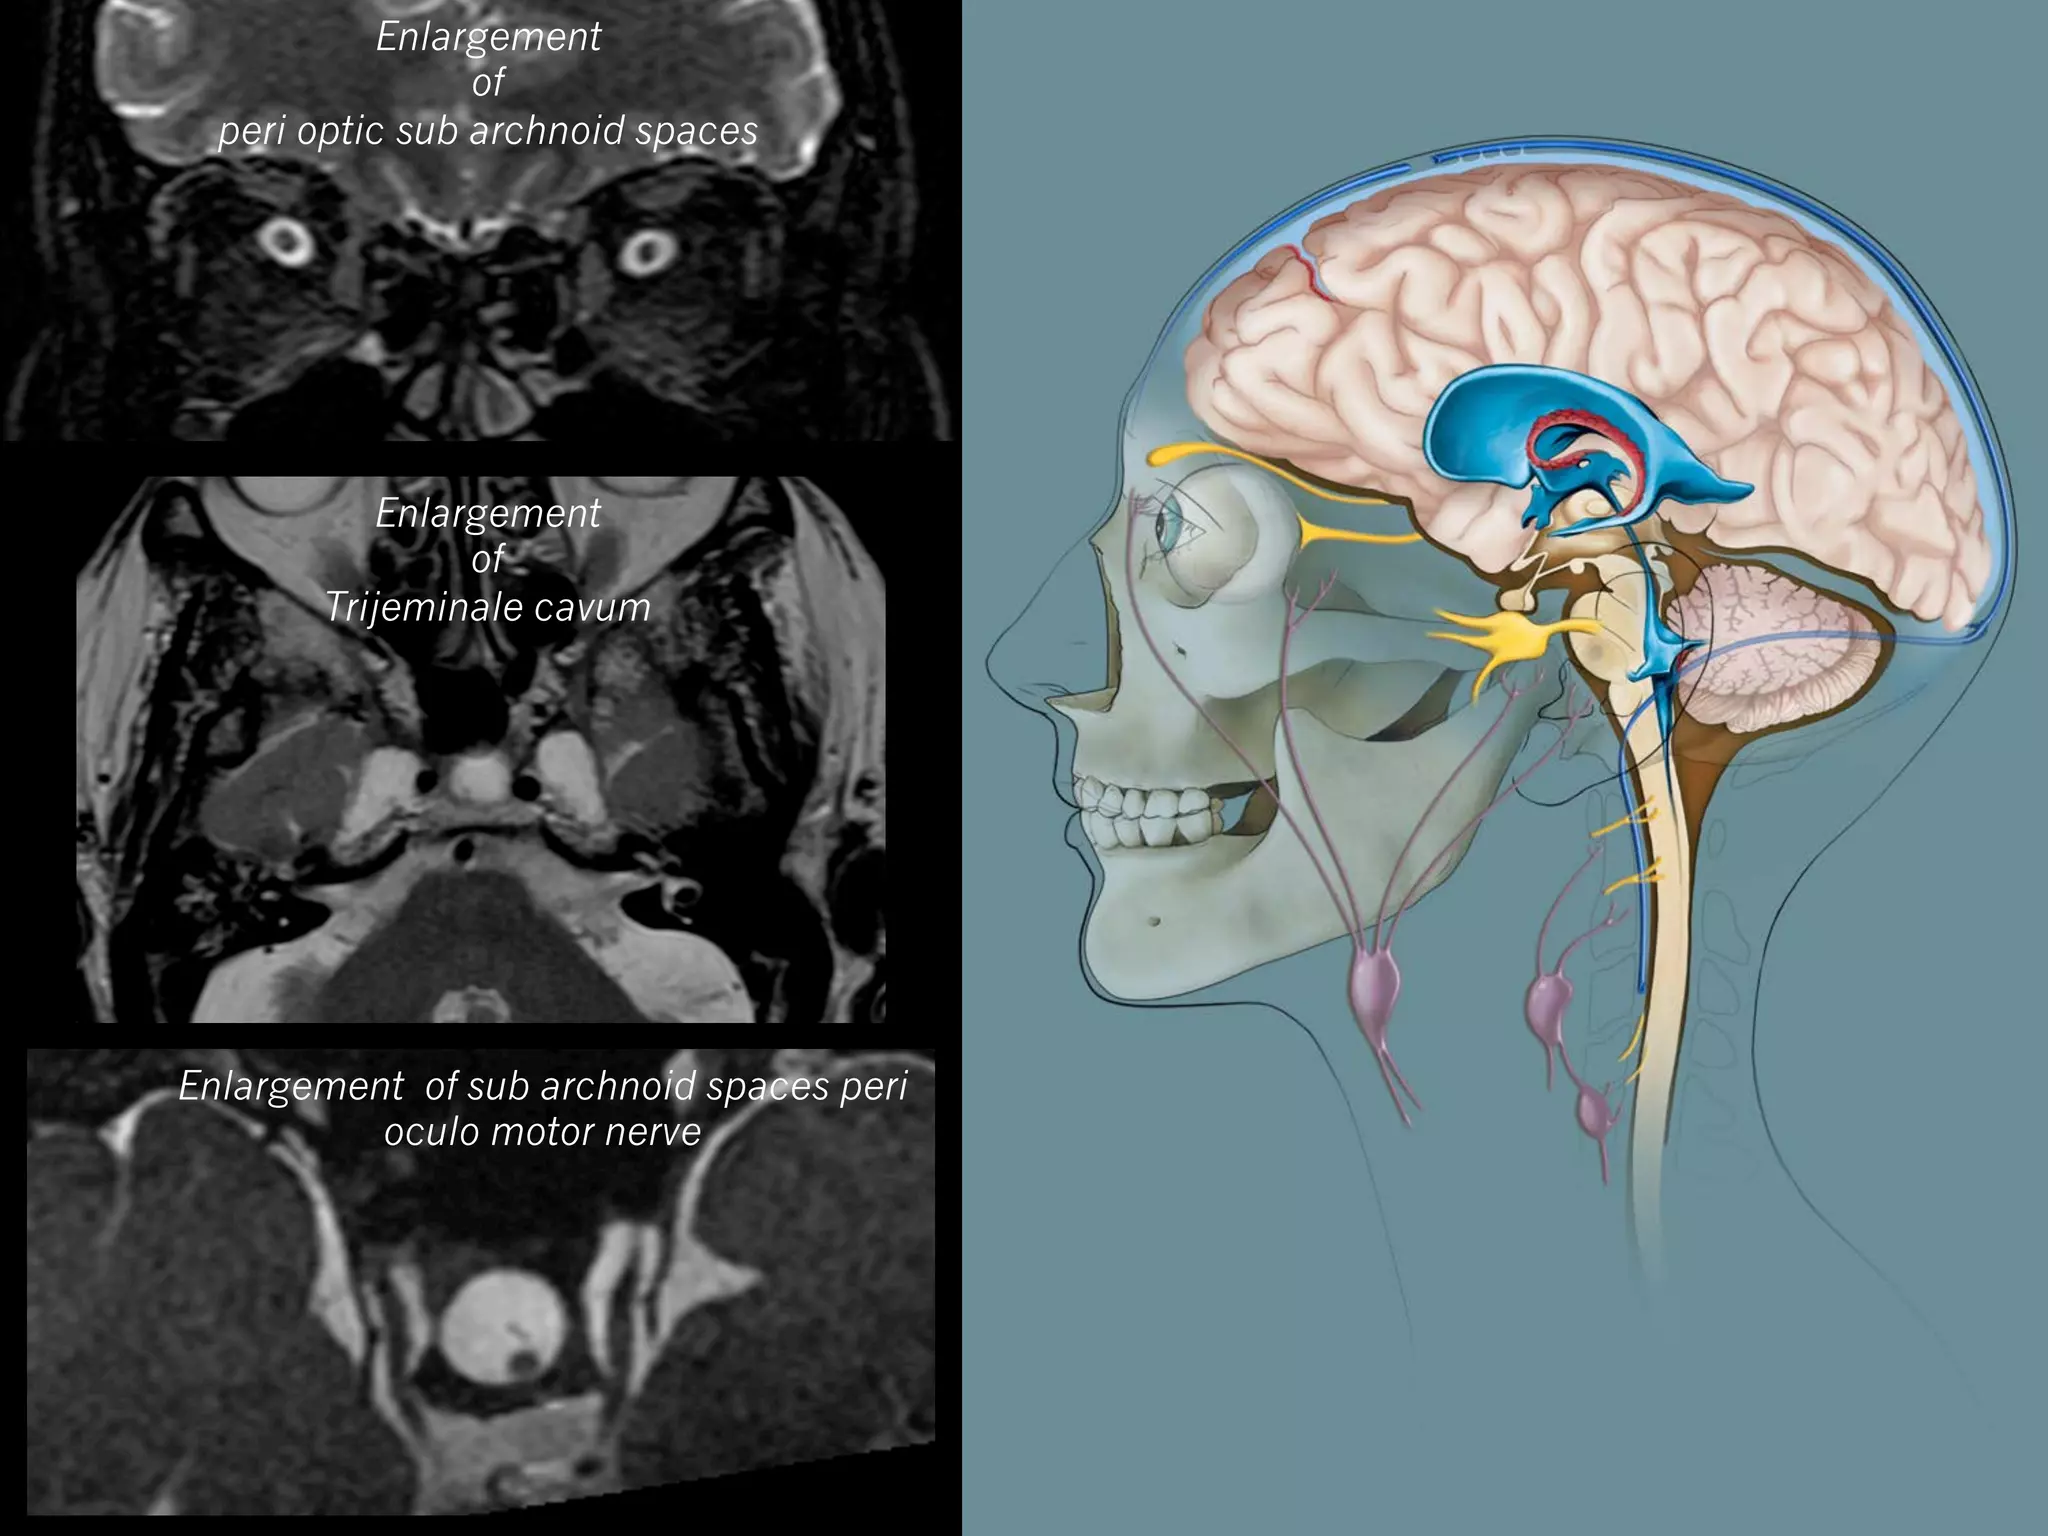

Axial (or frontal) T2w : orbital exploration +++

—  Enlargement of peri optic subarachnoid space (70%)

Enlargement

of

peri optic sub archnoid spaces

Trijeminale cavum

Enlargement of sub archnoid spaces peri

oculo motor nerve

MRI Axial (or frontal)T2w : orbital exploration +++ —  Tortuous optic nerves (> 7O%) —  Enlargement of peri optic subarachnoid space (70%) —  Flattening of posterior globe (45%)

3D FSE T2 Emptysella Time : 3’30 Tortuous optic nerves Enlargement of peri optic sub archnoid spaces

Enlargement of peri optic subarchnoid spaces Enlargement of Trijeminale cavum Enlargement of sub archnoid spaces peri oculo motor nerve